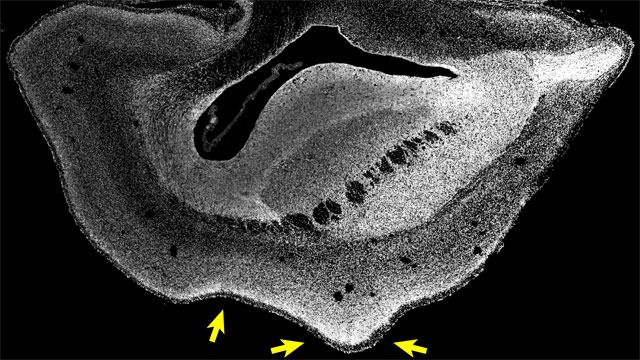

과거 연구팀은 인간 유전자를 주입하자 원숭이 태아의 대뇌 신피질(neocortex) 두께가 일반 원숭이 태아의 2배, 뇌주름은 인간 태아 수준으로 발달함을 알아냈다.

실제로 왼쪽 사진은 일반적인 원숭이 태아의 뇌이지만, 오른쪽 사진은 인간 유전자를 삽입하고 난 뒤 촬영한 원숭이 태아의 뇌다.